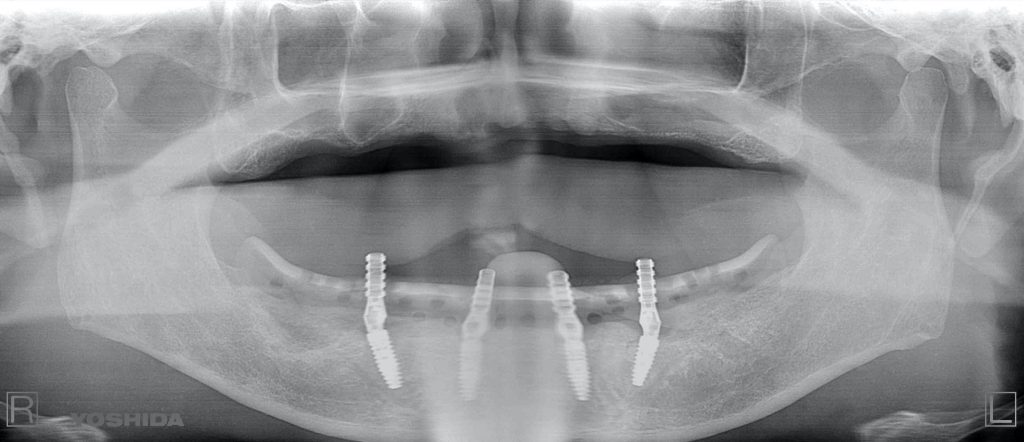

下記の症例は全ての歯を抜歯しなければいけない無歯顎患者さんにインプラントと同時に固定式の歯を装着する事ができる治療方法で最小本数である4本のインプラントで12本分の歯を支える形になり、費用を抑え、最小限のインプラント本数でQOLの回復を劇的に高めます。

これをオールオン4と呼びます。

オールオン4 約350万円(税抜)